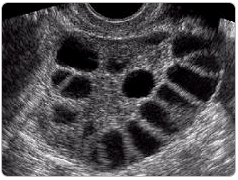

PKOS'ta Sık Görülen Bulgular